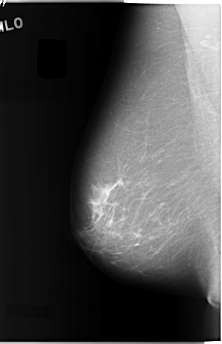

C_0040_1.LEFT_MLO

LEFT_MLO LINES 5944 PIXELS_PER_LINE 3096 BITS_PER_PIXEL 12 RESOLUTION 50 OVERLAY